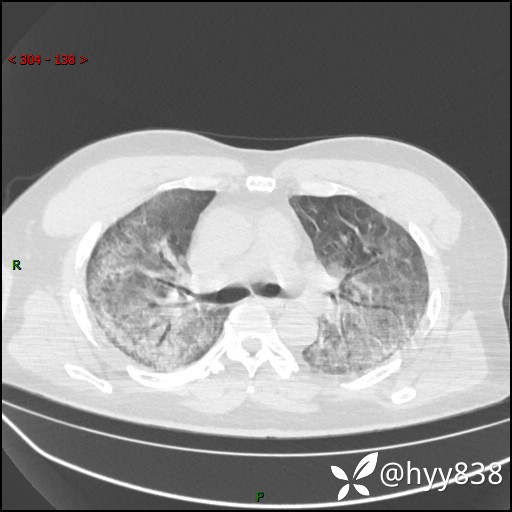

辅助检查:CT

临床诊断:间质性肺炎

第二次CT(7天后)